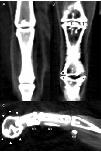

Figure 3. Reconstructed dorsal plane CT image of a normal MTP and IP joint (A), reconstructed dorsal plane CT image of a severely affected MTPjoint and IP joint (B) with periarticular new bone formation (as- terisks *) and new bone formation within the joint space (daggers â ), and reconstructed sagittal plane CT image of a severely affected digit (C) with a misshaped distal phalanx surrounded by a rim of new bone (arrowheads â²) and linear mineralization plantar to the digit within the extensor tendons (NB).